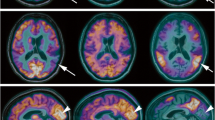

Besides the direct measurement of Aβ plaques, μPET imaging can help in the characterisation and phenotyping of animal models of AD by taking advantage of radiotracers already implemented in the clinical application for diagnosis in AD like, e.g., [18F]FDG, [11C]MP4A or [11C]FMZ. As already pointed out, non-invasive small animal PET imaging allows the assessment of AD imaging parameters at definite times and this repetitively over time within the same animal. In a knock-out mouse model for the brain/neuron-specific insulin receptor (NIRKO), Schubert et al. [36] investigated the influence of neuronal insulin resistance in neurodegeneration and could demonstrate reduced Akt and GSK3β phosphorylation and hyperphosphorylation of tau protein in NIRKO mice as compared to controls. Speculations on the regulative role of neuronal insulin receptors on cerebral glucose metabolism led to the performance of μPET analyses with NIRKO mice in vivo with [18F]FDG in collaboration with our group. In this study, tg and control animals underwent [18F]FDG-PET as well as in vivo high-resolution μMRI for co-registration aspects to differentiate distinct brain regions and hypermetabolic active harderian glands and to ensure proper region-of-interest analysis. Brain-to-background ratios for [18F]FDG uptake in NIRKO mice did not show any significant difference as compared to control animals (Fig. 1) suggesting that, in this specific study, insulin signalling did not have a substantial influence on basal brain glucose metabolism detectable by μPET.

Unaltered spatial learning, long-term memory and brain glucose metabolism in NIRKO mice. a Escape latency to find the platform after exposure to the water maze for 7-week-old control (open circles) and NIRKO (filled circles) mice. Data presented per session represent the mean of four trials per session and the mean of seven animals of each genotype±SEM. b Escape latency to find the platform after exposure to the water maze for 11-month-old control (circles) and NIRKO (triangles) mice. Data are separated for mice having performed a Morris water maze task at the age of 7 weeks (experienced mice, open symbols) and those that have not before encountered a Morris water maze task (naive mice, filled symbols). Data presented per session represent the mean of four trials per session and the mean of four to seven animals of each genotype±SEM. c. Shown are representative high-resolution MRI (upper) and matched [18F]FDG-μPET images (lower) through the brain of a representative control mouse (upper) and a representative NIRKO mouse (lower) [transaxial (left), coronal (center), and sagittal (right)]. ROI were placed in a transaxial plane (arrow). Distinction between brain and hypermetabolic harderian glands (arrowhead) is made by co-registration with MRI (from Schubert et al. [36] with permission, copyright 2004 by the National Academy of Science)

A subsequent study included multi-tracer PET imaging in an AD mouse model in collaboration with Heneka et al. [37]. Using APP23 tg mice, Heneka et al. [37] investigated the effect of locus ceruleus (LC) degeneration [by induction with N-(2-chloroethyl)-N-ethyl-bromo-benzylamine (dsp4)] and its contribution to AD pathogenesis. Biochemical and histological findings demonstrated loss of LC neurons, depletion of noradrenaline (NA), increase in microglial and astroglial activation and an increase in amyloid plaques in specific brain regions after dsp4 treatment. The loss of NA was also associated with increased cognitive deficits in APP23 tg animals. To investigate the effect of LC degeneration in this mouse model, we performed multi-tracer μPET imaging assessing cerebral glucose metabolism, acetylcholine esterase activity and FMZ binding. For this purpose, three different sets of animals have been analysed performing [18F]FDG-, [11C]MP4A- and [11C]FMZ-PET. The different sets compared (1) non-treated APP23 with wild-type mice at 10 and 13 months of age, (2) dsp4- and control-treated tg as well as wild-type mice 4 weeks after treatment and (3) APP23 tg mice with and without dsp4-treatment 4 and 12 weeks after dsp4-application. The results showed no significant differences in the non-treated APP23 tg versus wild-type animals at baseline or after aging. Most importantly, tg mice receiving the dsp4-treatment differed significantly from non-treated tg animals 4 weeks after the treatment in FMZ binding and acetylcholine esterase activity. Moreover, 12 weeks after LC degeneration, significant differences for all three radiotracers ([18F]FDG-, [11C]MP4A- and [11C]FMZ) could be detected indicating that LC degeneration and inflammatory reaction contributes significantly to AD pathogenesis (Fig. 2).

Altered cerebral glucose metabolism, neuronal integrity and cholinergic function detected in vivo after noradrenergic depletion of APP23 mice. a Representative high-resolution MRI (first row) and matched representative [18F]FDG, [11C]FMZ and [11C]MP4A μPET images (second–fourth rows, coronar is left; transaxial, middle; sagittal, right) through the brain of saline-treated (left panel) and dsp4-treated APP23 (right panel). b Quantification of [18F]FDG, [11C]FMZ and [11C]MP4A uptake in saline-treated wild-type (wt-con) and saline-treated APP23 (tg-con) mice at 13 months of age. No significant differences were detected. c Quantification of [18F]FDG, [11C]FMZ and [11C]MP4A uptake in saline-injected (tg-con) and dsp4-treated (tg-dsp4) APP23 tg mice at the same age revealed a decrease in all parameters after LC degeneration (mean±SEM; n = 4 animals per group; Student’s t test; *p < 0.05; from Heneka et al. [37] with permission, copyright 2006 by the Society for Neuroscience)